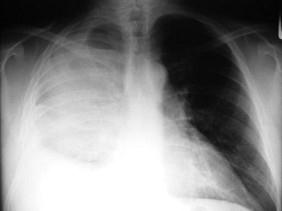

男,59岁,呼吸困难,胸痛,有发热,请结合CT图像选择最可能的诊断 ( )A、肺囊虫病B、肺癌C、肺脓肿D、大叶性肺炎E、脓胸

问题 男,59岁,呼吸困难,胸痛,有发热,请结合CT图像选择最可能的诊断 ( )

选项 A、肺囊虫病 B、肺癌 C、肺脓肿 D、大叶性肺炎 E、脓胸

答案 E